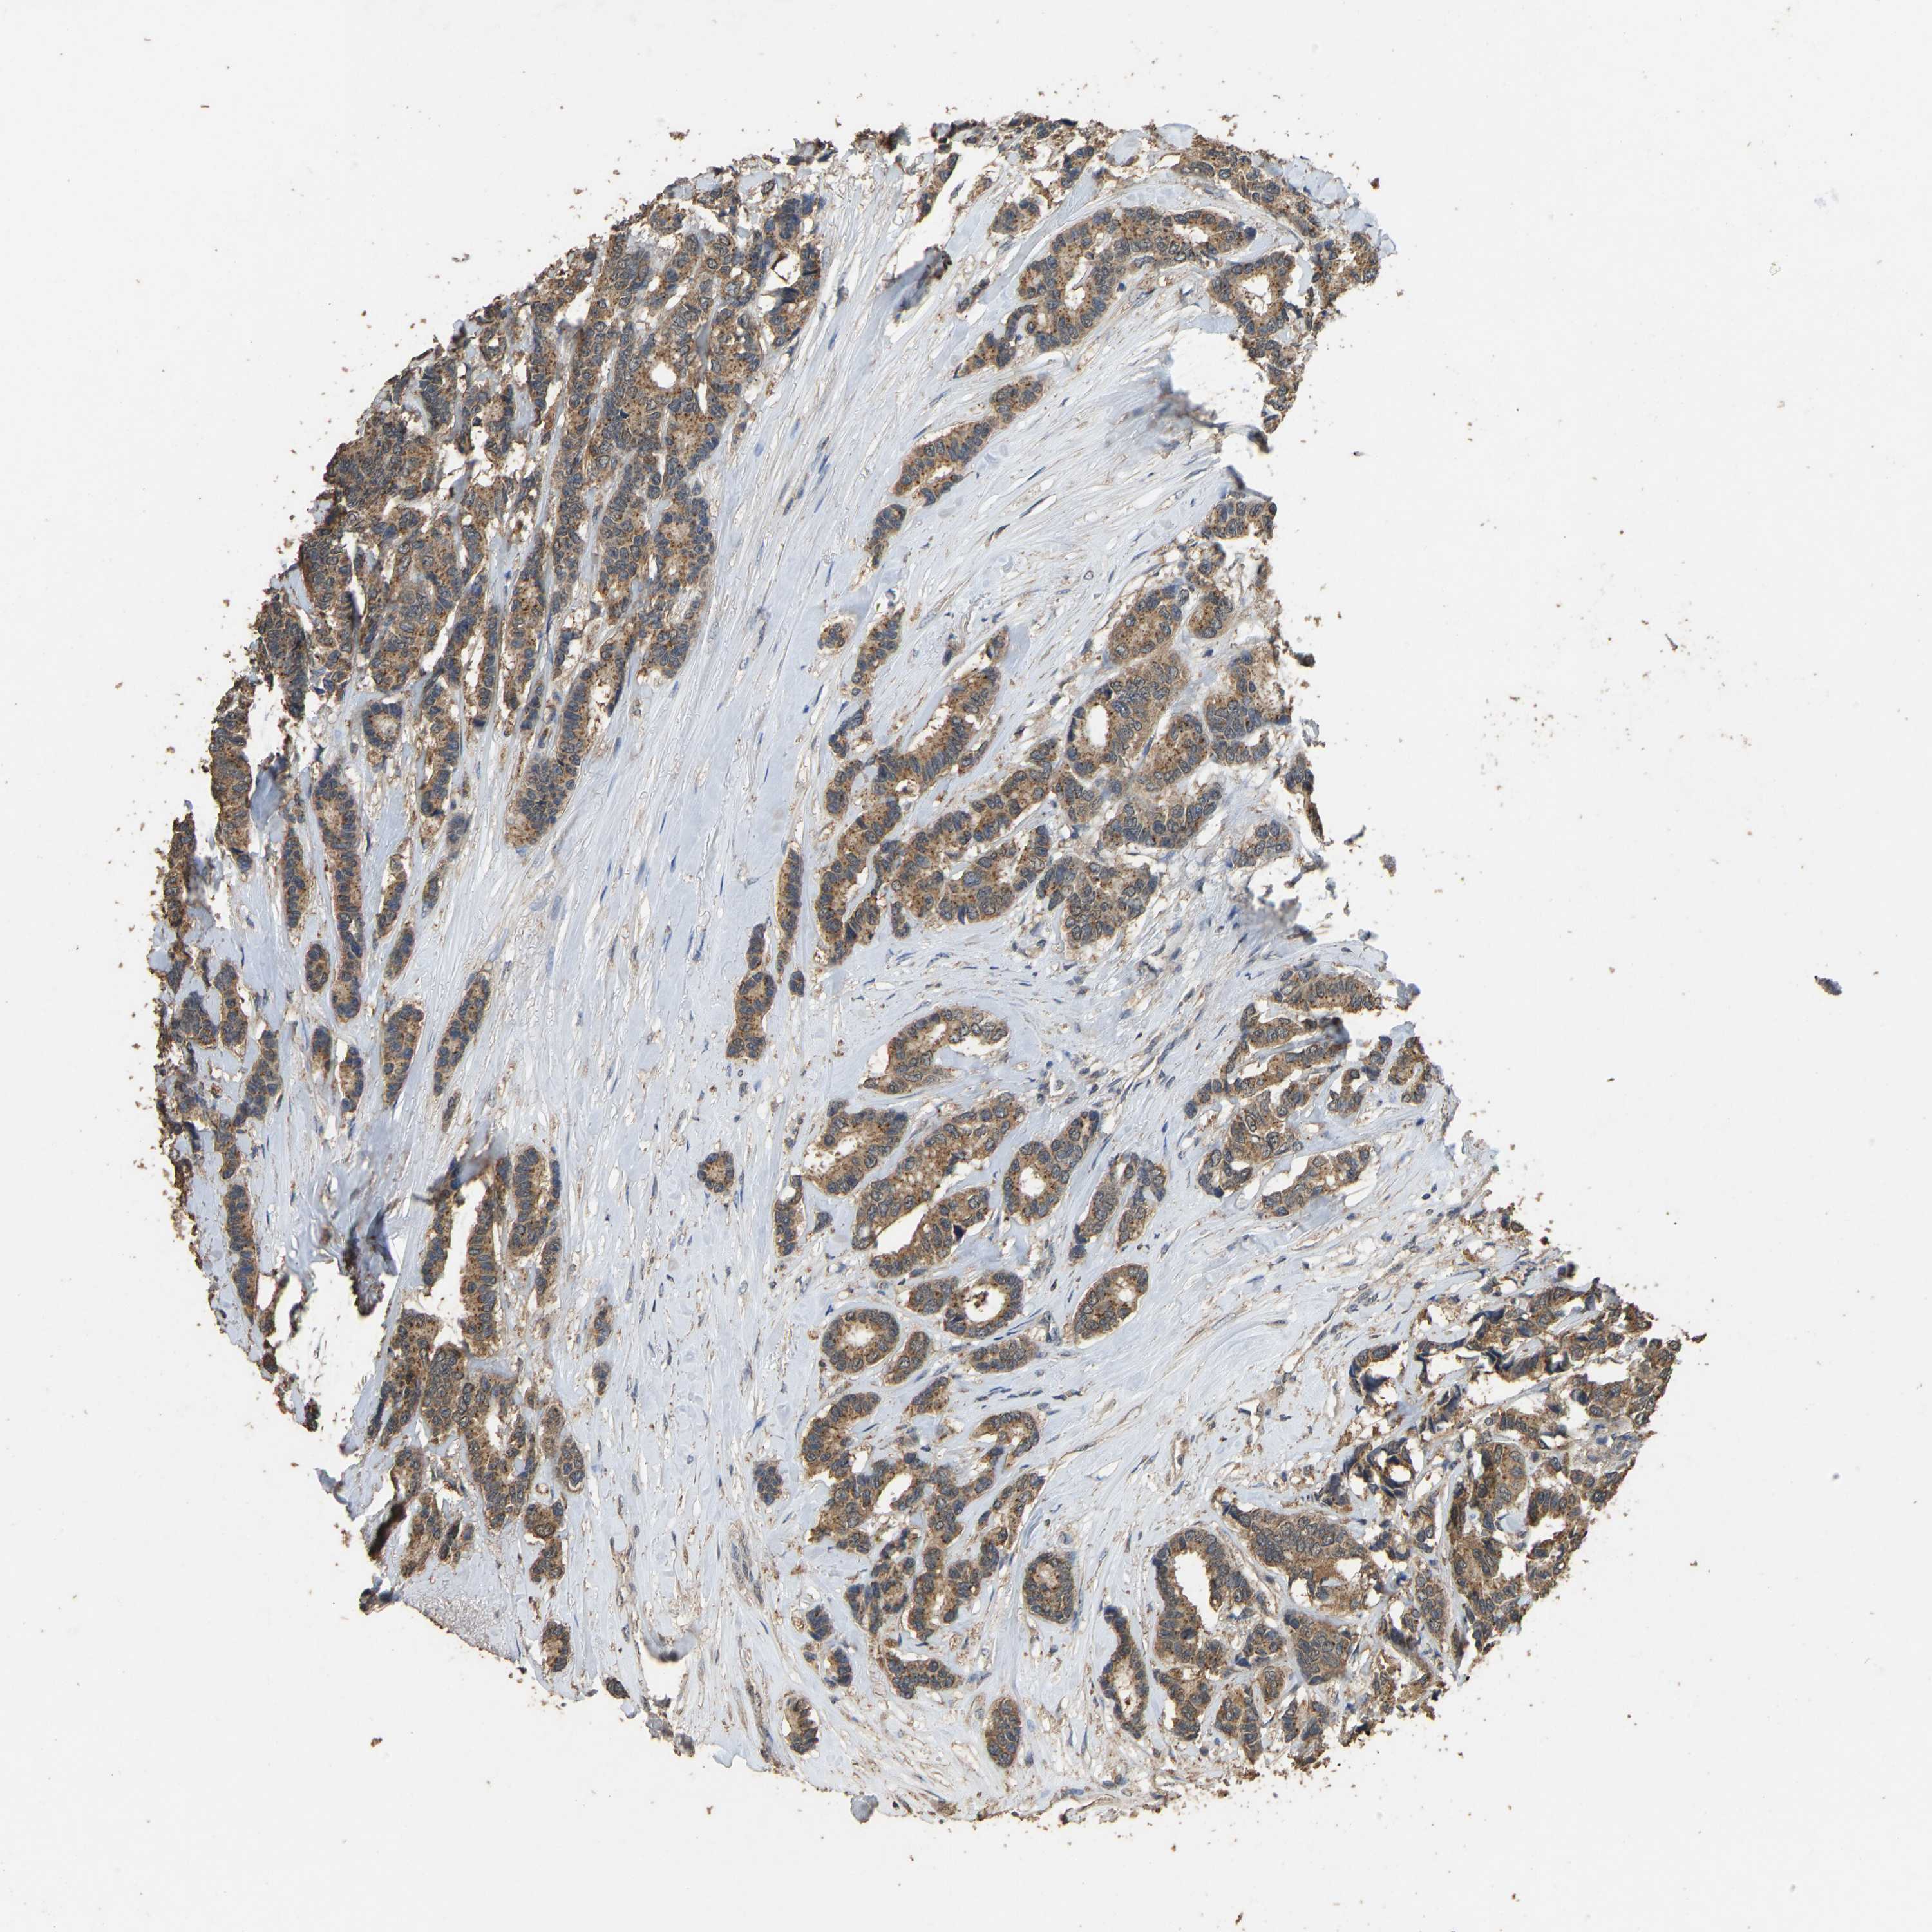

CANCER BREAST CANCER Show tissue menu

BRCA TCGA BRCA VALIDATION PROTEIN EXPRESSION